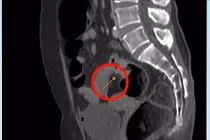

1.jpg

Các cơ quan chức năng tại hiện trường vụ việc.